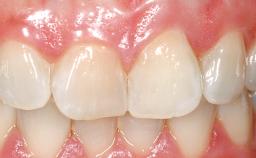

Late Placement of an Implant in a Maxillary Left Central Incisor Site

A 30-year-old female patient had lost tooth 21 and was referred to our clinic for consultation and treatment. Due to advanced apical infection, tooth 21 had been extracted two months earlier at another clinic and an acrylic-resin tooth had been bonded to the adjacent teeth. The patient desired implant treatment to avoid any damage to the adjacent natural teeth. While the patient had no history of any systemic disorder, she was a heavy smoker and exhibited medium to advanced periodontitis in the entire jaw. After the initial treatment to achieve a pocket probing depth of less than 4 mm and no bleeding on probing, a decrease in the height of the papillae mesial and distal to the extraction site and overall gingival recession were observed.